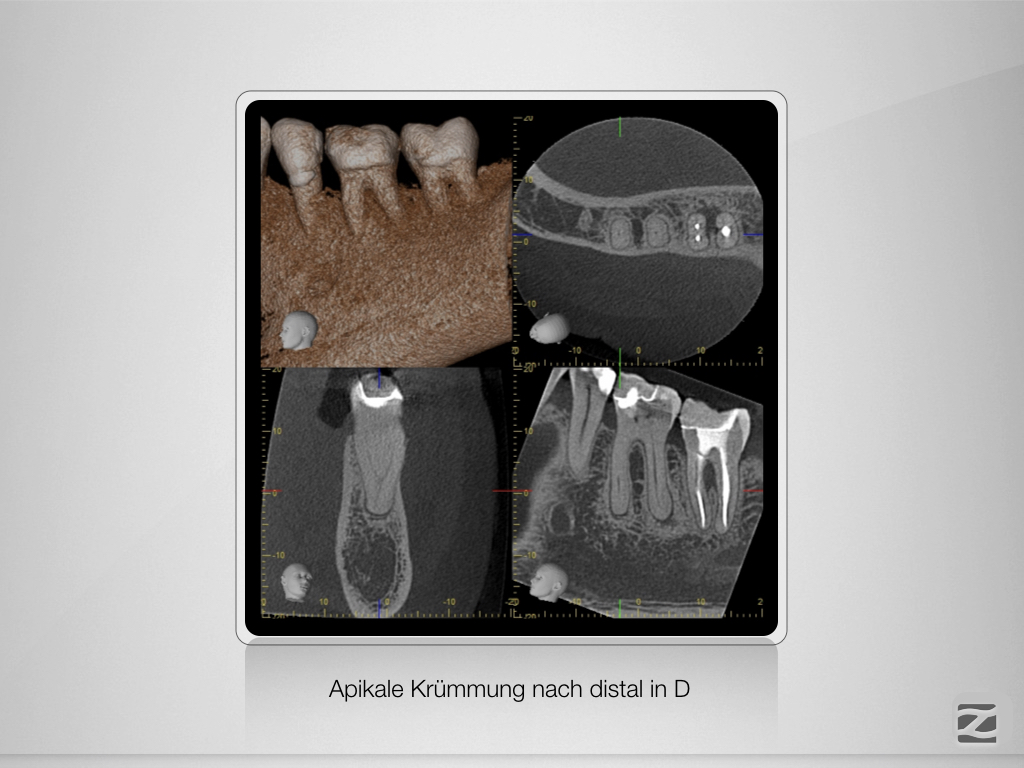

36D.004

Planung leicht gemacht